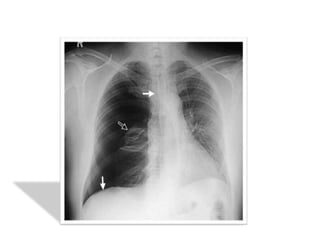

on recherchera systématiquement les signes

radiologiques associés :

• Une opacité liquidienne à niveau horizontal de la base

témoignant d’un hydropneumothorax

• Position du médiastin et du cœur éventuellement

refoulé

• Anomalies parenchymateuses homo ou contolatérales

en sachant qu’il existe une surcharge vasculaire réflexe

du coté sain

• Un aspect de petit cœur dans les formes bilatérales

 Tuberculose pulmonaire :

• Le PNO résulte

- soit par rupture dans la cavité pleurale de

caverne ou caseum sous pleural

- soit par séquelles paracicatricielles

• Le diagnostic : facile devant des signes d’appel

cliniques et radiologiques confirmé par la

présence des BAAR dans l’examen des crachats

• Tableau clinique souvent aigu

• La RX du thorax met en évidence une ou

plusieurs cavités avec niveau hydroaériques